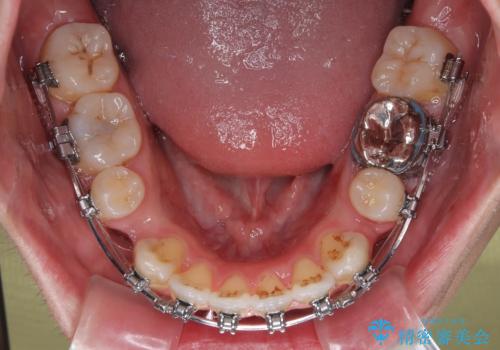

- 矯正装置

- メタルブラケット

抜歯したスペースを活用して前歯を後ろへ下げることで、口元の突出感を大きく改善。

奥歯の噛み合わせがずれている「シザーズバイト」を適正に整えることで、見た目だけでなく機能性も向上し、安定した咬合が獲得できました。